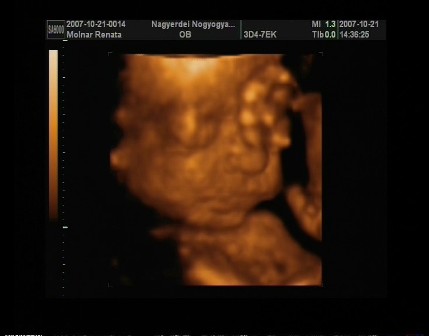

Egézséges kislányom lessz!Néhány fotó!!!! Kép Kép Kép Kép

m. reni

Nagyon jó képek! Annyira édes ahogy dörzsöli a szemét!!! :wink: